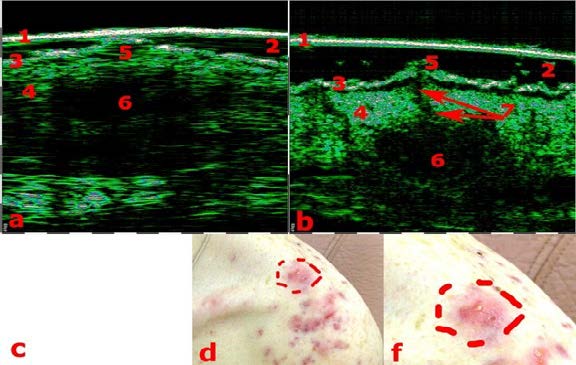

Η διαφοροποίηση μεταξύ των Υπερτροφικών Ουλών (1η εικόνα) και των Χηλοειδών (2η εικόνα) με τη βοήθεια του Υπέρηχου Υψηλής Συχνότητας.

Φλύκταινες (1η εικόνα) και συνδυασμός οζιδίων και κυστών (2η εικόνα). Οι πιο έντονες αλλαγές εντοπίζονται στο πάχος του χορίου. Σαρώσεις με Υπέρηχο Υψηλής Συχνότητας και Βιντεοδερματοσκοπικές απεικονίσεις.

ΔΙΑΦΟΡΟΠΟΙΗΣΗ ΜΕΤΑΞΥ ΥΠΕΡΤΡΟΦΙΚΩΝ ΟΥΛΩΝ ΚΑΙ ΧΗΛΟΕΙΔΩΝ

Οι ουλές του δέρματος αποτελούν ένα από τα πολύτιμα θέματα στην δερματολογία και την αισθητική ιατρική. Σύμφωνα με ορισμένες πρόσφατες μελέτες, ελήφθησαν δεδομένα HFUS για τη διαφοροποίηση των διαφόρων τύπων ουλών.

Οι μετρήσεις ουλών HFUS και η ανάλυση των μοτίβων χρησιμοποιήθηκαν με επιτυχία για τη διαφοροποίηση των νορμοτροφικών, υπερτροφικών, χηλοειδών και ατροφικών ουλών. Αυτές οι κλινικές πληροφορίες είναι ζωτικής σημασίας για την ορθή θεραπεία και αποκατάσταση των ουλών.

Η διαφοροποίηση μεταξύ των υπερτροφικών (αριστερά) και των χηλοειδών ουλών (δεξιά).

ΕΚΤΙΜΗΣΗ ΤΗΣ ΣΟΒΑΡΟΤΗΤΑΣ ΤΗΣ ΑΚΜΗΣ

Η εξέταση ακμής με HFUS είναι χρήσιμη για την ακριβή διάγνωση της μορφής της ακμής {φλεγμονώδης/μη φλεγμονώδης, φλύκταινες, συνεστιώδης : βαθιά φλεγμονώδη οζίδια, αποστήματα και συρίγγια που συνδέονται κάτω από το δέρμα, δημιουργώντας ομάδες βλαβών κυρίως στον κορμό και στους γλουτούς, αφήνοντας ουλές) κ.λπ.}.

Για παράδειγμα, η σοβαρότητα της ακμής πολύ συχνά υποτιμάται, επειδή οι εσωτερικές αλλαγές στο χόριο και κάτω είναι αόρατες.

Η εξέταση με HFUS επιτρέπει την εμφάνιση των σημείων διήθησης, εξίδρωσης και ίνωσης, γεγονός που επιτρέπει τη διάγνωση του τύπου της ακμής και την εφαρμογή της κατάλληλης θεραπείας, με έλεγχο της αποτελεσματικότητας της θεραπείας με HFUS.